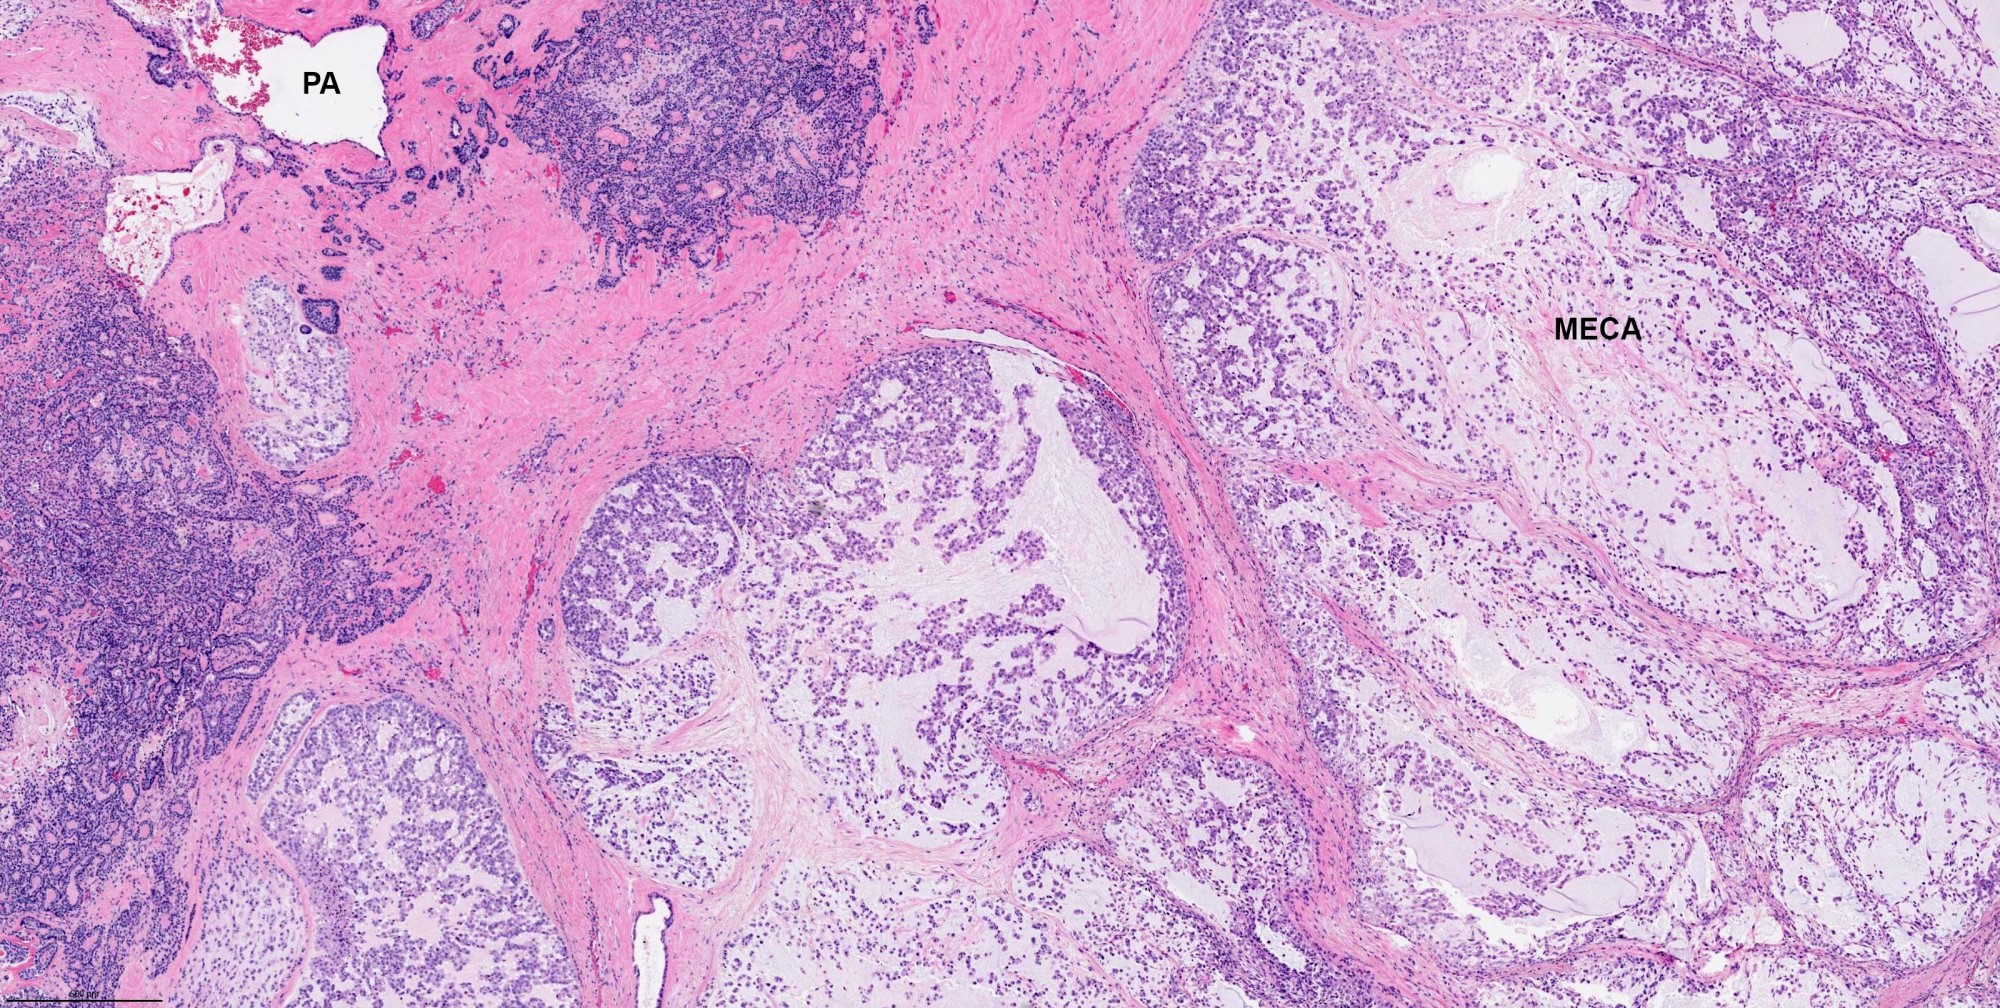

- Invasiveness is typically demonstrated as expansile invasive multinodular growth: myoepithelial carcinoma rarely shows infiltration of single cells / small clusters or desmoplastic reaction

- Nodules often have a hypocellular center with hyalinized stroma or bland necrosis surrounded by a hypercellular peripheral zone

- Tumor necrosis can be seen within the hypercellular central zone of a tumor nodule

- Currently, there is no well defined, widely accepted grading system: presence of tumor necrosis is considered by some as a feature of high grade myoepithelial carcinoma (Am J Surg Pathol 2015;39:931)

- Presence of pre-existing / residual pleomorphic adenoma component can be seen in myoepithelial carcinoma ex PA

Contributed by Abeer Salama, M.D. and Bin Xu, M.D., Ph.D.